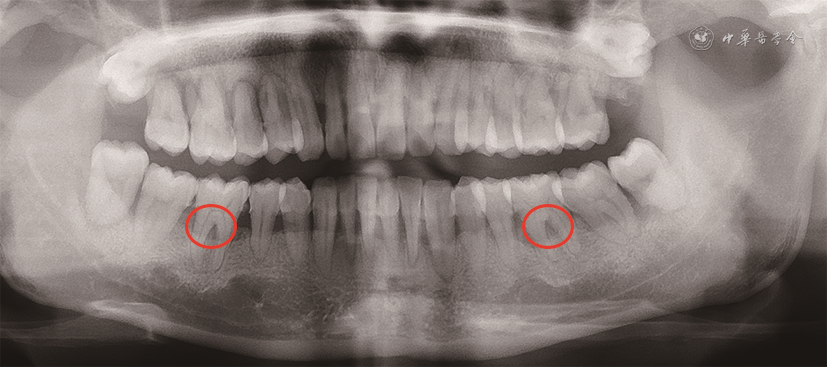

根分叉病变的诊断主要根据探诊和影像学检查。由于根分叉区的解剖结构特点,临床医师需使用特殊弯曲的根分叉探针——Nabers探针进行临床探诊。探诊时将Nabers探针置于根分叉入口冠方牙面上,再将探针以Z字形向根方移动,若探针可探及根分叉凹陷处,则为检测到根分叉病变(图1)。影像学诊断中,X线片对诊断根分叉病变有较大意义(图2),但二维影像学技术受投射角度及组织影像重叠影响,仅可提示根分叉病变的存在可能,必要时需借助锥形束CT进一步完善影像学检查[12, 13](图3)。

此外,牙髓感染、牙根折裂等潜在问题也需在检查根分叉病变时予以关注。由于牙本质小管、侧副根管等结构的存在,牙髓组织和牙周组织在健康、功能和疾病方面相互影响。根分叉病变临床诊疗管理时不能忽视患牙潜在的牙髓问题。这对患牙的疗效预测和治疗方案设计有重要意义。牙根折裂可导致局部牙槽骨快速丧失,当牙根折裂发生于根分叉区附近的根面时,可直接导致根分叉病变。临床需对单个牙位的牙槽骨大量破坏时刻保持警惕,锥形束CT等影像学检查可辅助早期诊断,减少患者的治疗时间和经济负担。